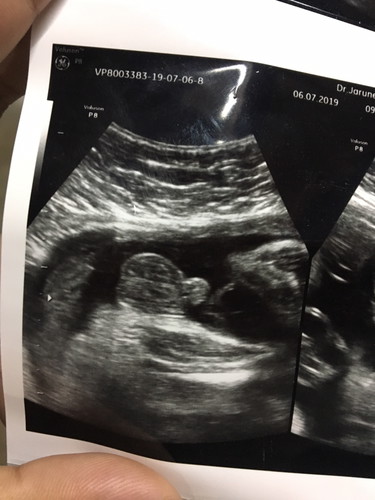

แม่ๆช่วยดูหน่อยค่ะว่า. ผู้หญิงหรือผู้ชาย ใจอยากได้ผู้หญิง. ?

ไข่อลังการมากแม่ บ้านนี้ลูกสาวค่ะใจอยากได้ลูกชายเพราะมีลูกสาวคนนึงเเล้ว

จู๋ชัดมากแม่ 🤣